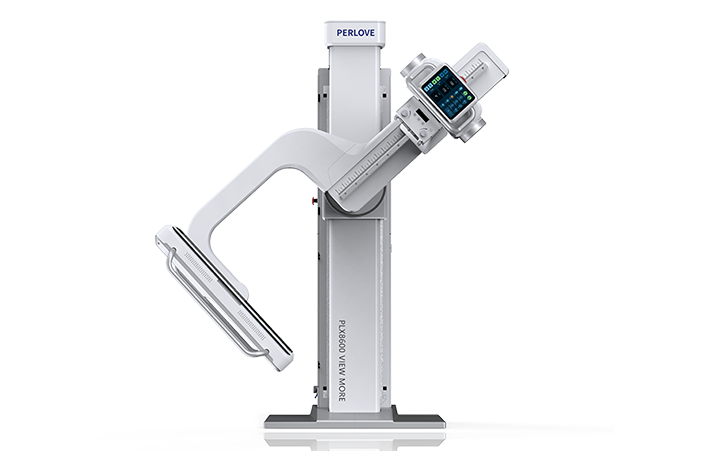

PLX R8600

大視野平板動態DR

一板成像 豈止于大 PLX R8600

一板成像 豈止于大 PLX R8600

支持全脊柱攝影、雙下肢攝影、脊髓造影、復雜創傷、人工關節置換、關節損傷的修復重建等大視野臨床應用

17"*34"有效視野,一次成像不拼接。相較于多張攝影再軟件拼接的DR設備,PLX8600解決了拼接圖像存在密度不均勻,拼接處圖像配準和放大效應等問題,給臨床帶來了大視野影像解決方案,可一次性覆蓋全脊柱或雙下肢影像。

除常規靜態攝影外,PLX8600大平板具備動態透視和點片功能,透視采集功能可支持大視野、多角度的可視化觀察。通過可視化的動態影像,配合點片功能,能夠很好的觀察復雜部位病灶,有效的抓取關鍵幀,降低患者多次攝片的概率。如:全脊柱狀態評估、長骨關節活動度、下肢靜脈造影瓣膜功能評估、消化道功能評估、脊髓造影等更多大視野臨床應用。

高功率大熱容,為持久工作保駕護航。不管是攝影模式還是透視模式,均能保持長時間連續工作,無需預約,隨到隨拍。